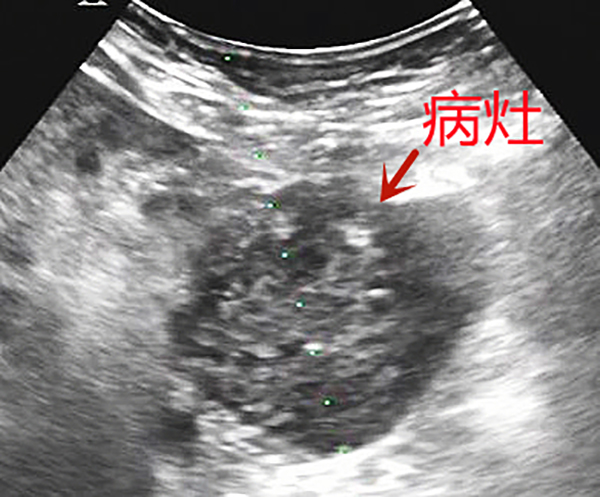

55歲的曹大叔咳嗽、咳痰3個(gè)多月了,在外院做增強(qiáng)CT提示胰腺占位性病變,為求進(jìn)一步診治,他來到我院腫瘤科就診。為了制定合適的治療方案,腫瘤科三病區(qū)主任陳日新和主治醫(yī)師王磊黎、石周綜合評(píng)估后,建議實(shí)施超聲引導(dǎo)下經(jīng)腹胰腺穿刺活檢術(shù)以明確病理診斷。

超聲科張步林主任及張煒副主任在接到腫瘤科的會(huì)診請(qǐng)求后,認(rèn)真分析,根據(jù)胰腺腫瘤位置、大小、壞死范圍,反復(fù)評(píng)估與周圍重要臟器的解剖關(guān)系,權(quán)衡相對(duì)安全的穿刺路徑,考慮到術(shù)中可能因?yàn)榛颊吆粑鼊?dòng)度的變化造成穿刺路徑偏移,術(shù)前多次跟患者溝通進(jìn)行憋氣練習(xí),并且計(jì)劃利用超聲科的介入法寶——超聲穿刺探頭,通過兩個(gè)大血管之間幾毫米的微小間隙進(jìn)行超聲引導(dǎo)下進(jìn)針,避免傷到周圍組織及大血管。

一切準(zhǔn)備就緒,超聲實(shí)時(shí)引導(dǎo)下,局麻、進(jìn)針、精準(zhǔn)避開血管、到達(dá)腫瘤表面、激發(fā)活檢槍、順利取材、迅速拔出,憑借張步林主任和張煒副主任的實(shí)踐經(jīng)驗(yàn),整個(gè)過程一氣呵成。